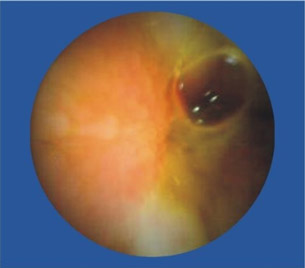

李女士,46岁。患有腹痛、腹泻、慢性肠炎等病史。肛门处轻度下坠感、偶有大便时肛门疼痛。口服胃肠药物,偶有缓解,但反复发作。经常规胃镜、肠镜、B超等检查未发现特殊病变,后到四川肛肠就诊车洪英主任结合腹痛部位考虑小肠病变可能,建议李女士做胶囊内镜检查,李女士在了解了胶囊内镜的检查原理及适应症、禁忌症后欣然接受此项检查。后经过胶囊内镜详细检查,确定了病变位置,然后李主任制定了详细的治疗方案,经过我院详细的治疗,李女士最后康复。

便血,去做检查,痔疮、胃镜、纤维结肠镜都做后,的出结论——小肠流血,但结肠镜够不着,还是看不见在具体位置。因此,也算是体验了下高科技,胶囊内镜。试过后真是感叹,这玩意儿真厉害!比普通药丸子稍大,一喝水下去了。自动掉头,自动拍照,自动传输。拉出来后找护士要了些消毒药水洗了下,细细观察。发现镜头口径有点小最多1mm,确实是高科技,这么小的东西,包括了拍照(可能是2个小时内的连续拍照),无线信号传输,方向姿势控制等等,厉害。

近日,67岁的陈爷爷因为便血导致严重贫血,胃镜、肠镜都做了却查不出病因。被转送到四川肛肠医院后,陈爷爷本来以为要再接受一次痛苦的内镜检查,没想到,医生给出的检查方式却是要他吞下一颗“胶囊”,同时穿上一件连着各种数据线的背心。很快,医生就发现陈爷爷的小肠上面存在一个不断出血的溃疡,经过手术,医生终于治好了陈爷爷的“怪病”。陈爷爷吞下的其实是一种叫“OMOM胶囊内镜”的检查仪器,主要用于小肠疾病的排查。